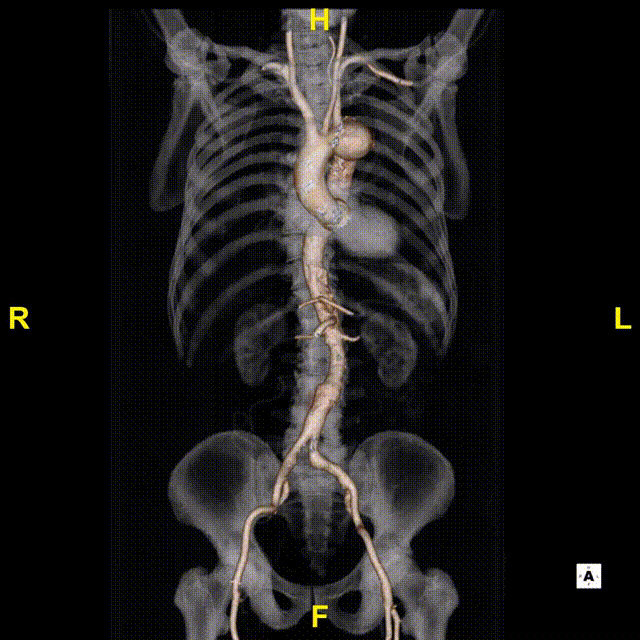

术前CTA

术前CTA可见,患者解剖复杂,Ⅲ型弓,偏心型弓部动脉瘤。

斑马导丝是治疗什么的「胸有乾坤」至简至易 行之有效—— Zone 0 TBE植入治疗弓部动脉瘤病例报道_https://www.jmylbn.com_新闻资讯_第6张

术前3D重建

测量数据: